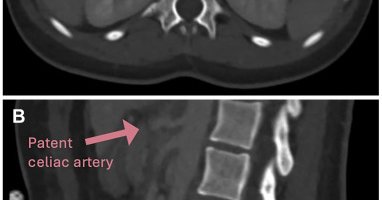

π©»β οΈ Rare trauma complication. This case highlights endovascular repair of a hepatic artery pseudoaneurysm with celiac dissection & intramural hematoma after blunt abdominal trauma, showing the power of minimally invasive management. π https://t.co/F9sOXcp1OU

#VascularTrauma

jvscit.org

Hepatic artery pseudoaneurysm is a concerning yet rare complication of blunt abdominal trauma, with treatment recommended upon diagnosis.1 Endovascular repair of hepatic artery aneurysms has gained...